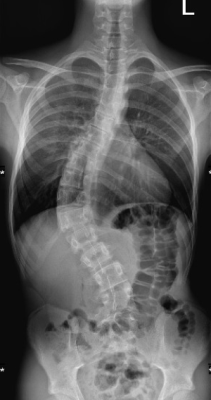

Skoliose

Unter Skoliose versteht man eine dauerhafte Seitverbiegung und Rotation der Wirbelsäule mit gleichzeitiger Verdrehung der Wirbelkörper. Nach ihrer Herkunft lassen sich verschiedene Formen unterscheiden (idiopathisch, kongenital, neuromuskulär, adult), die sich hinsichtlich des Erkrankungsalters, der Ausprägung, des Fortschreitens der Erkrankung und der möglichen Behandlungsverfahren unterscheiden.